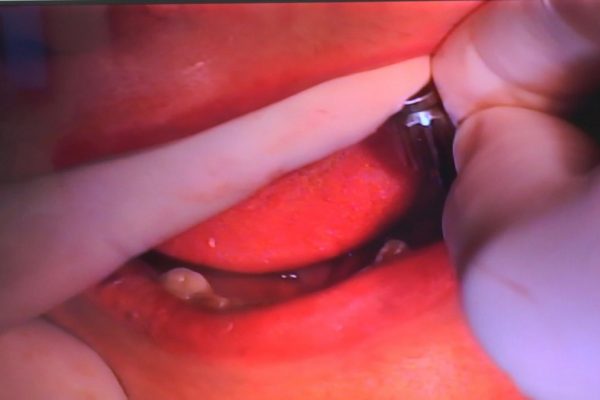

W ostatni weekend czerwca 2018 roku kursanci II Sezonu Preludium Implantologii odbyli piątą, finałową sesję, która w całości podporządkowana była praktyce. W ciągu dwóch dni zabiegowych Lekarze uczestniczący w szkoleniu przeprowadzili szereg zabiegów pod kierunkiem dr n.med. Violetty Szycik. Wszczepili 17 implantów oraz przeprowadzili ekstrakcje i zabiegi regeneracyjne kości. Zabiegi były wykonywane także w sedacji dożylnej z udziałem specjalisty anestezjologii i intensywnej terapii dr Jolanty Grzybowskiej. Preludium implantologii to nowy program edukacyjny dla adeptów implantologii stomatologicznej, którego celem jest wprowadzenie do implantologii poprzez pozyskanie wiedzy w szerokim zakresie i uwzględnieniem szczegółów mających decydujące znaczenie dla powodzenia leczenia implantologicznego. Ale tak jak wszystkie szkolenia w Instytucie Vivadental, w tym wiodące Practiculum Implantologii, zorientowane jest na praktyce i samodzielnym wykonywaniu zabiegów pod kierunkiem Mentora. To najlepsza edukacja w medycynie zabiegowej, a zarazem najlepszy start do implantologii.